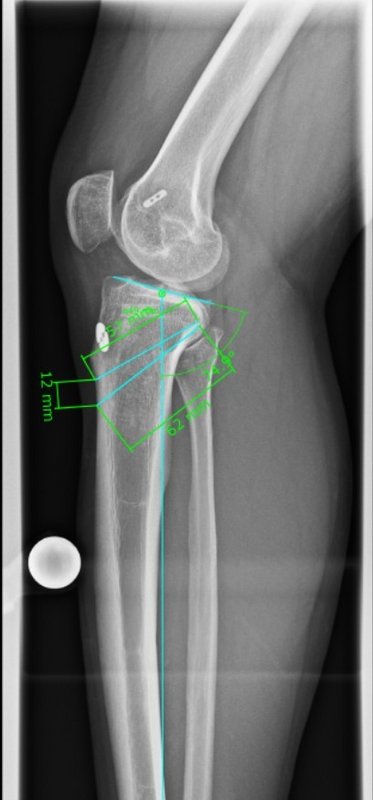

Beinachsfehlstellungen

Manchmal liegen Beschwerden Fehlstellungen zu Grunde – sei es im Sinne eines „O-Beins“ bzw. eines „X-Beins“, aber auch eine Rotationsfehlstellung kann ursächlich für Beschwerden des Kniegelenkes sein. Gerade bei Knorpelschädigungen und Arthrose ist eine Fehlstellung mit konsekutiver Überlastung einer Gelenkhälfte oftmals ursächlich. Durch den Ausgleich der Fehlstellung wird die Biomechanik des Gelenkes wieder hergestellt und das betroffene Areal entlastet. Wir bieten Umstellungen in allen Ebenen (O-Bein, X-Bein, Rotationsfehlstellungen, pathologischer Slope, …) an. Oft ist es sogar möglich, dass eine notwendige endoprothetische Versorgung nochmals lange hinausgezögert werden kann, was vor allem jungen Patienten zu Gute kommt.

Re-Ruptur des vorderen Kreuzbandes

Im Falle von Re-Rupturen des vorderen Kreuzbandes ist in manchen Fällen keine direkte einzeitige Versorgung mit einem neuen Kreuzband möglich, z.B. wenn sich die Bohrkanäle geweitet haben. Dann müssen die alten Kanäle in einem ersten Eingriff gefüllt werden und die erneute Kreuzbandplastik erfolgt nach einigen Monaten. Auch Achs-Fehlstellungen, die das Risiko einer weiteren Ruptur begünstigen würden, werden abgeklärt. Insbesondere eine X-Bein-Stellung oder eine Verkippung des Schienbeinkopfes (sog. „Slope“) gelten hier als Risikofaktoren, die ggf. vor einer erneuten Versorgung mit einem Kreuzband behandelt werden müssen – ebenso wie periphere Instabilitäten, die ebenfalls mit abgeklärt werden müssen.